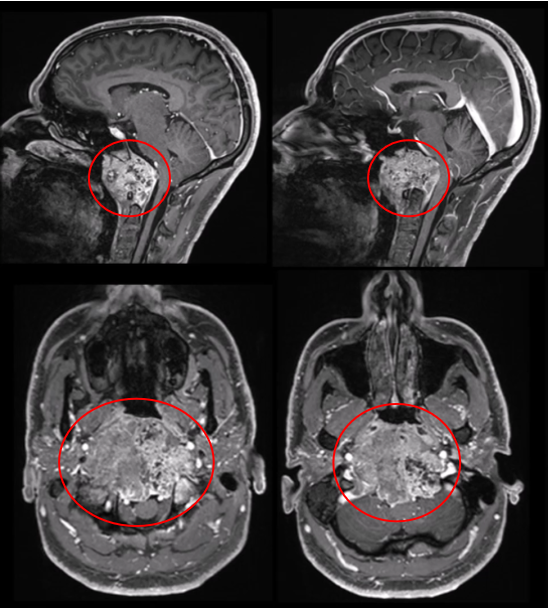

MRI和CT扫描显示巨大颅颈交界区脊索瘤,肿瘤最大直径达10cm、瘤体积96.5cm³,肿瘤并向双后外侧延伸浸润性生长,较多侵犯右侧,肿瘤延伸至椎前间隙、下斜坡、双侧枕骨髁、第一颈椎C1的前弓以及C2的齿状突,巨大肿瘤压迫脑干和双侧椎动脉移位,并向硬膜内压迫扩张。

▼术前MRI

▼C:术前MR显示肿瘤巨大延伸,并浸润长入硬膜内的脑实质。F:术后MR显示全切肿瘤和脑干延髓占位压迫得到解除。